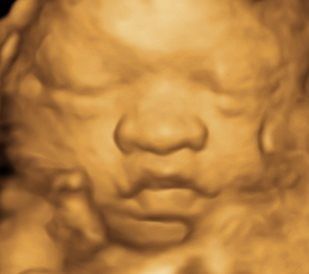

A Little Insight is proud to announce that we now offer 8K technology. This is the most realistic & amazing view of your unborn baby.

A Little Insight is an elective ultrasound center dedicated to providing a private experience that focuses on you and your baby, and we believe that every parent deserves to maximize their prenatal experience. Our 3D/4D & 5D ultrasounds provide an opportunity for you to see your baby not only in still image but in real-time motion. Why wait until your baby is born to celebrate his/her life?

A Little Insight 3D/4D/5D Ultrasound is unique because we truly offer the finest 3D/4D & 5D prenatal experience available. We combine cutting-edge technology with a family theater environment to bring you incredible images of your unborn baby in the womb. Best of all, we offer an unparalleled bonding experience that you and your family can cherish for a lifetime!